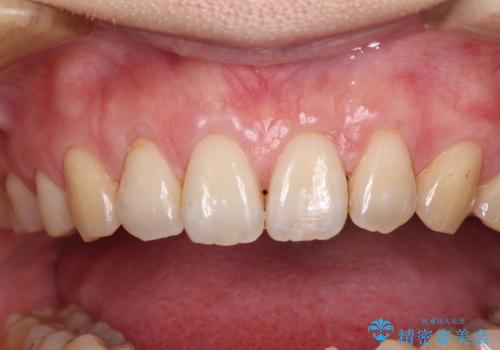

必要な被覆量が多かったため、満足のいく被覆を達成するには2度の手術が必要と思われましたが、生着がよく、術後の注意事項を徹底したことで、十分な被覆量を達成することができました。

矯正治療で退縮してしまった歯肉 歯肉移植で自然な前歯に